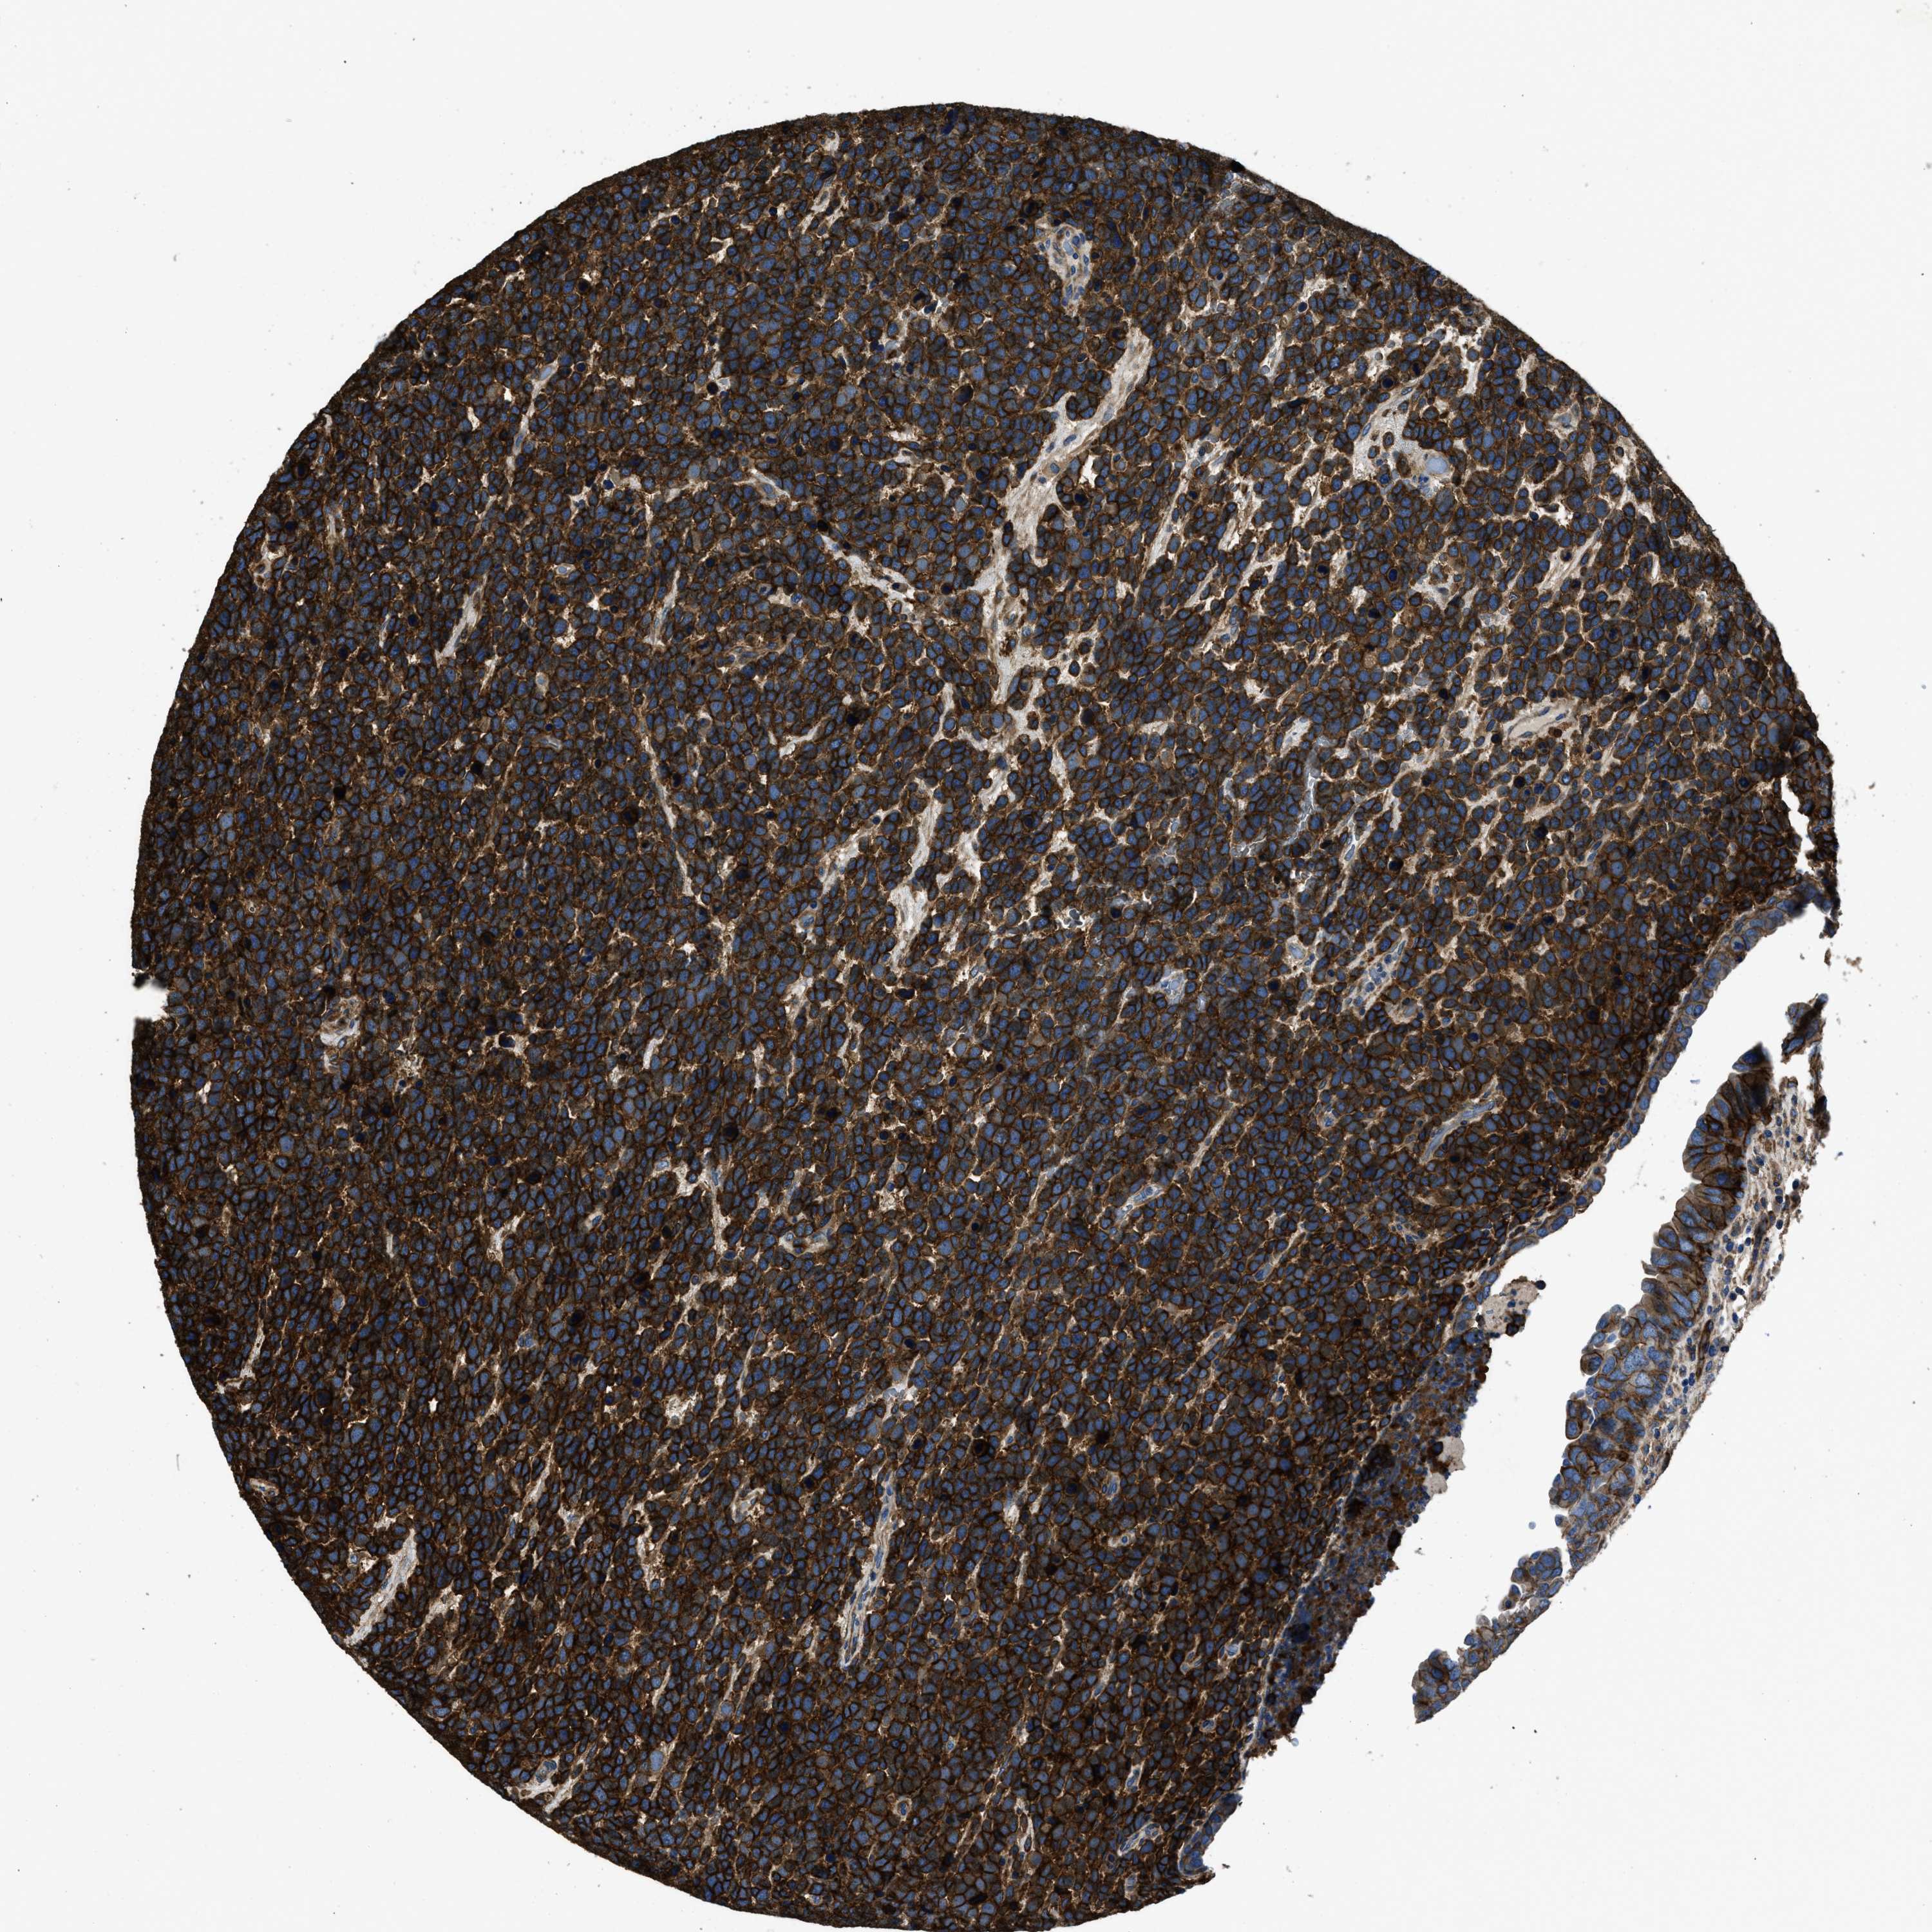

UROTHELIAL CANCER - Protein expressioni

A mouse-over function shows sample information and annotation data. Click on an image to view it in a full screen mode. Samples can be filtered based on level of antibody staining by selecting one or several of the following categories: high, medium, low and not detected. The assay and annotation is described here.

Note that samples used for immunohistochemistry by the Human Protein Atlas do not correspond to samples in the TCGA dataset.

Antibody stainingi

Antibody staining in the annotated cell types in the current human tissue is reported as not detected, low, medium, or high, based on conventional immunohistochemistry profiling in selected tissues. This score is based on the combination of the staining intensity and fraction of stained cells.

Each image is clickable and will lead to virtual microscopy that enables deeper exploration of all samples and also displays staining intensity scores, fraction scores and subcellular localization as well as patient and tissue information for each sample.

Antibody HPA009285

Antibody HPA017139

Antibody CAB017826

Urothelial carcinoma, Low grade

Urothelial carcinoma, High grade